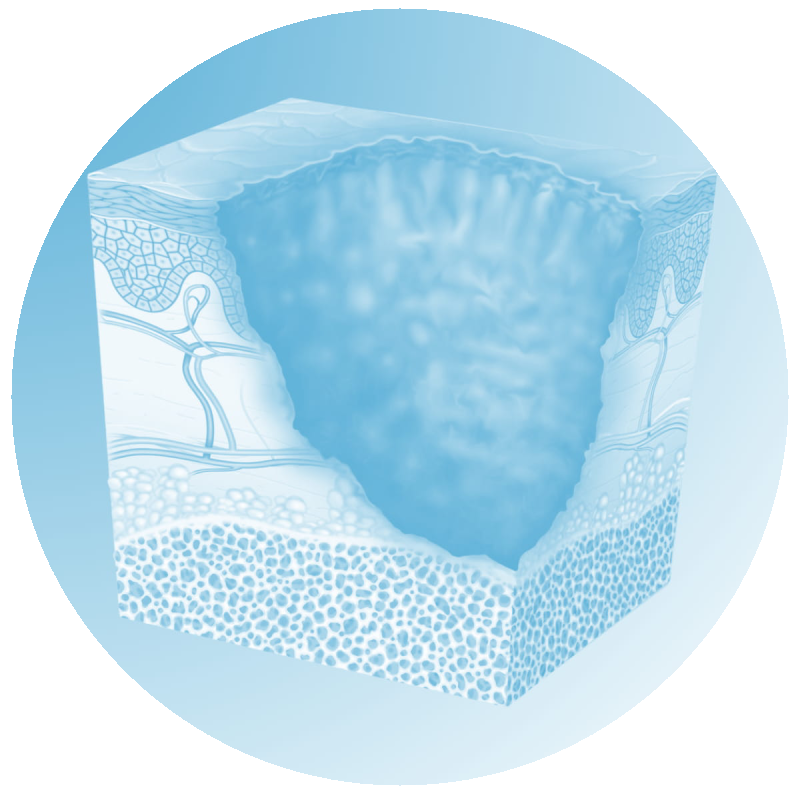

Cicatrización

Problemas crónicos de cicatrización y heridas.

La evidencia científica sugiere que MBST® puede influir en mecanismos endógenos al favorecer procesos fisiológicos del tejido. Estudios describen posibles efectos antiinflamatorios, analgésicos, inmunomoduladores y regenerativos, con un enfoque que busca apoyar tanto el síntoma como el origen del problema.¹

A nivel celular, se han reportado modulaciones en procesos como la señalización circadiana, la producción de ATP mitocondrial y el control del estrés oxidativo (ROS) y del entorno hipóxico. También se describen efectos sobre la respuesta inflamatoria y el potencial regenerativo en células endoteliales, cartilaginosas, óseas y nerviosas.